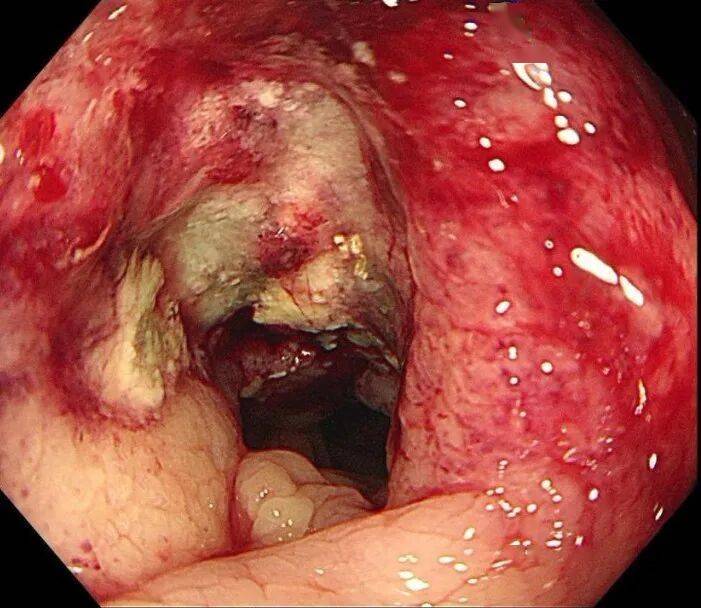

三天后,消化内镜中心孙舒仰医生操作的结肠镜顺利进行。当镜头探至升结肠近肝曲——正是之前查体摸到包块的位置时,一个不规则肿物赫然出现: 它环绕肠腔2/3,表面糜烂溃疡还附着污苔,质地脆弱一碰就出血,肠壁已变得僵硬,管腔也出现偏心性狭窄,万幸肠镜还能勉强通过。“高度怀疑结肠癌。”孙舒仰医生当场判断。

几天后的病理报告印证了这一结论:中分化腺癌。“原来腹痛、大便不成型是肠腔狭窄导致的不完全性肠梗阻,进食后压力增大就疼,排便后缓解。”医生解释道。从首次就诊到病理确诊,全程仅用6天,这背后是消化内科、影像科、内镜中心、病理科的高效协同作战。目前,王女士已转至肿瘤科和普外科接受进一步治疗。